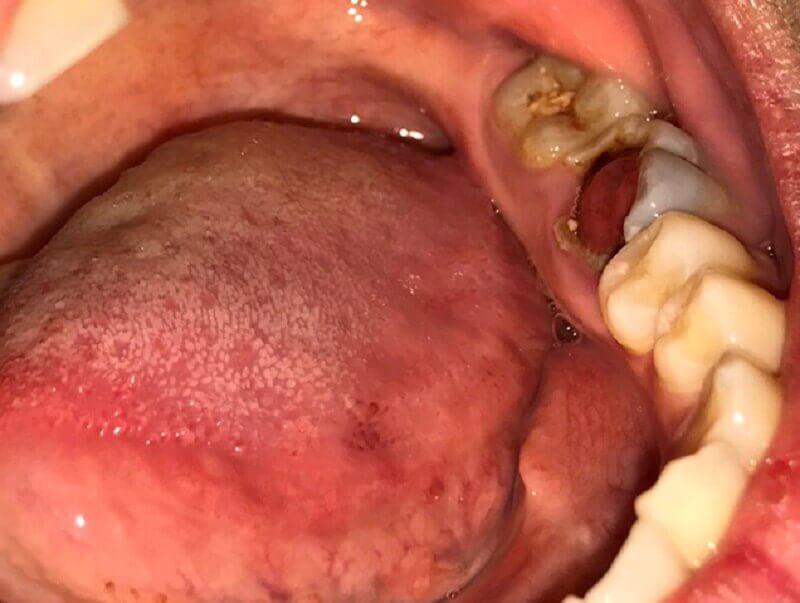

Răng sâu lồi thịt là hiện tượng vi khuẩn tích tụ trong khoang miệng gây viêm nhiễm khu vực xung quanh nướu răng khiến răn sâu nổi những phần thịt. Tình trạng này được các chuyên gia nha khoa cảnh báo là tình trạng cấp tính, vô cùng nguy hiểm.

Bên cạnh đó khi sâu răng ăn vào tủy không chữa trị kịp thời sẽ làm tủy răng bị thối và hoại tử gây ra lỗ dò, chịu tác động tấn công của vi khuẩn gây viêm đỏ, mưng mủ hoặc răng rò rỉ ra bên ngoài, sưng lên có hình dạng giống một cục thịt.

Răng sâu lồi thịt được xem là dạng áp xe răng, một trong những trường hợp sâu răng nguy hiểm đáng báo động. Răng sâu lồi thịt gây nhiều hệ lụy nghiêm trọng như nhiễm trùng tủy, hoại tử sàn miệng thậm chí là nhiễm trùng máu. Vì gây nhiều ảnh hưởng đến sức khỏe răng miệng, ảnh hưởng đến sức nhai và nhiều hệ lụy khác nên mọi người cần đặc biệt lưu ý đến tình trạng răng sâu này.

Khi đó, vi khuẩn sẽ tấn công nhiều vào nướu khiến khu vực này bị thối rữa, tạo ra lỗ dò thậm chí là gây hoại tử. Một thời gian sau, lớp niêm mạc xung quanh lỗ dò sẽ bị viêm nhiễm, mưng mủ, sưng tấy và trồi ra ngoài như cục thịt. Phần thịt lồi ra ngoài khiến người bệnh gặp nhiều trở ngại khi há miệng, ăn uống và khiến phần nướu gần đó bị nổi hạch.